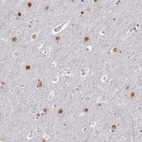

Immunohistochemical staining of human cerebral cortex shows nuclear positivity in neurons.